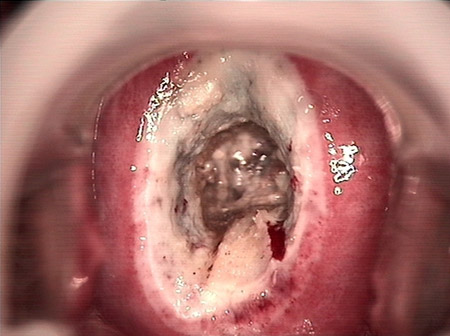

婦科leep錐切手術(shù) CIN2-3

CIN 2-3 leep術(shù)后